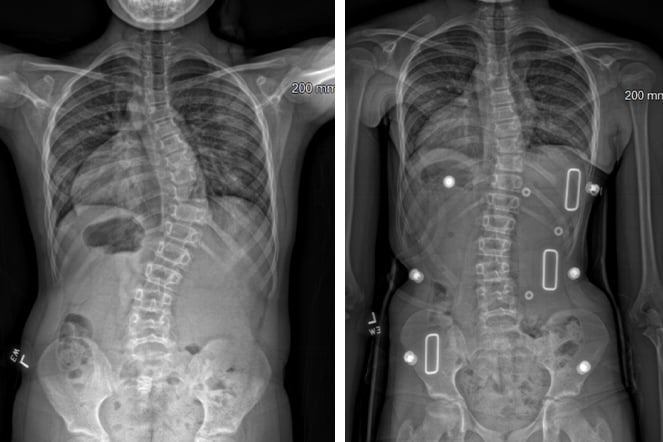

a before and after x-ray of a spine

X-rays of Chloe's spine before and after her VBT surgery.

At the time, she had never heard of bracing for scoliosis. Chloe began treatment with a back brace, an adjustment she found physically and emotionally challenging. “I felt kind of like a turtle,” she said, recalling moments of limited mobility and discomfort at school. Despite her best efforts and support from the POPS teams at both Shriners Children’s Erie and Shriners Children’s Philadelphia, bracing wasn’t enough to prevent curve progression. Eventually, surgery became the next step.

In 2021 Chloe underwent a vertebral body tethering (VBT) procedure, performed by pediatric orthopedic surgeon Joshua Pahys, M.D.